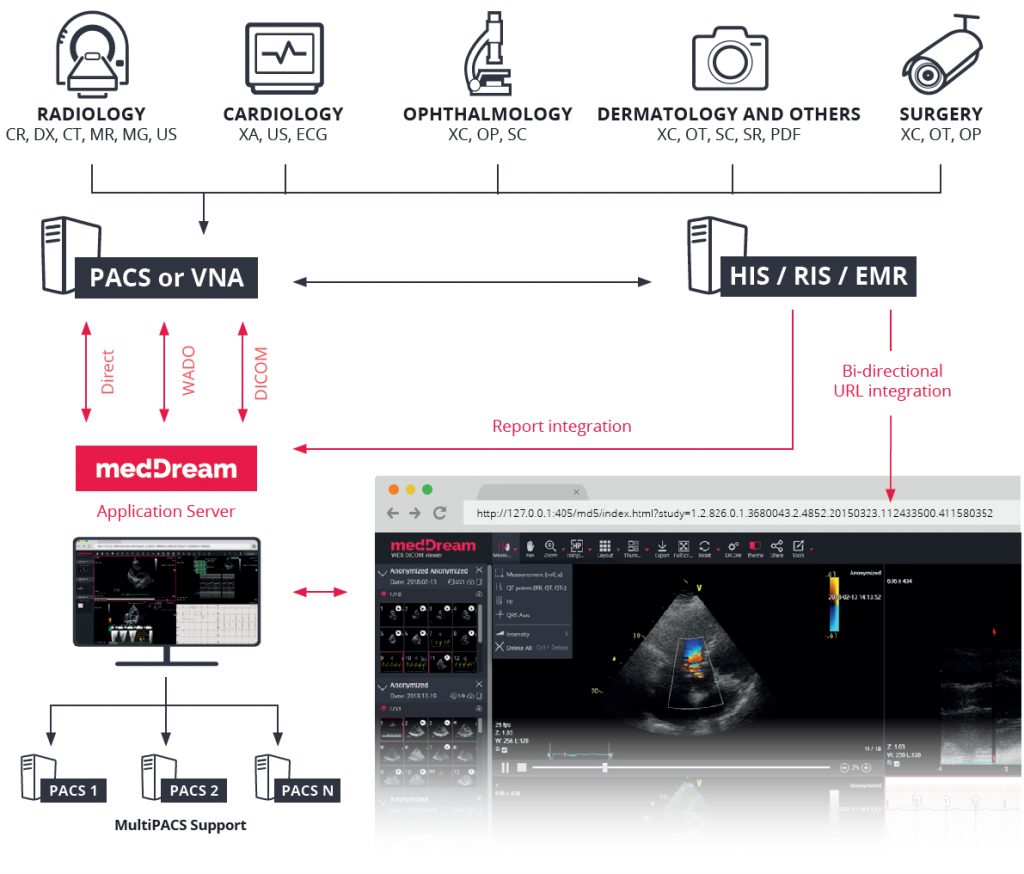

DICOM 3.0 compliant picture archiving and communication system. The PACS server provides connectivity to all DICOM modalities (CR, DX, CT, MR, US, XA, etc.). Review of DICOM images and diagnostics can be done using the MedDream WEB DICOM Viewer.Go to SitePad Editor to add your own text and edit me. It’s easy. Just Go to SitePad Editor to add your own text and edit me content and make changes to the font.

Vendor neutral and open integration interface archiveFeel